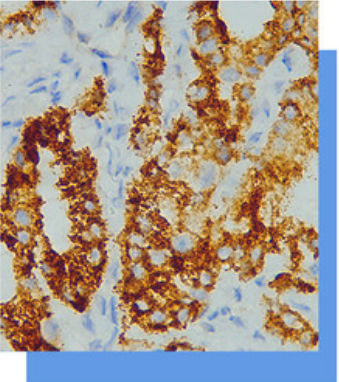

AMACR/p504s抗体试剂

AMACR又称p504s。P504S是- 种a甲酰基辅酶

A消旋酶,存在于正常组织中的胰腺、肝、肾小

管上皮和涎腺中,在尿道旁腺为均一的中等水平

表达。其主要表达于前列腺腺癌以及前列腺癌前

病变,在正常前列腺组织中只有极少为阳性表达

。最近研究表明P504S在结/直肠癌、胃癌、卵巢

癌、乳腺癌、肺癌、肾癌、肝细胞肝癌、淋巴瘤

和恶性黑色素瘤等肿瘤中也有阳性表达。女性生

殖系统来源的透明细胞癌通常阳性,而卵黄囊瘤

通常阴性。可以用于二者鉴别诊断。